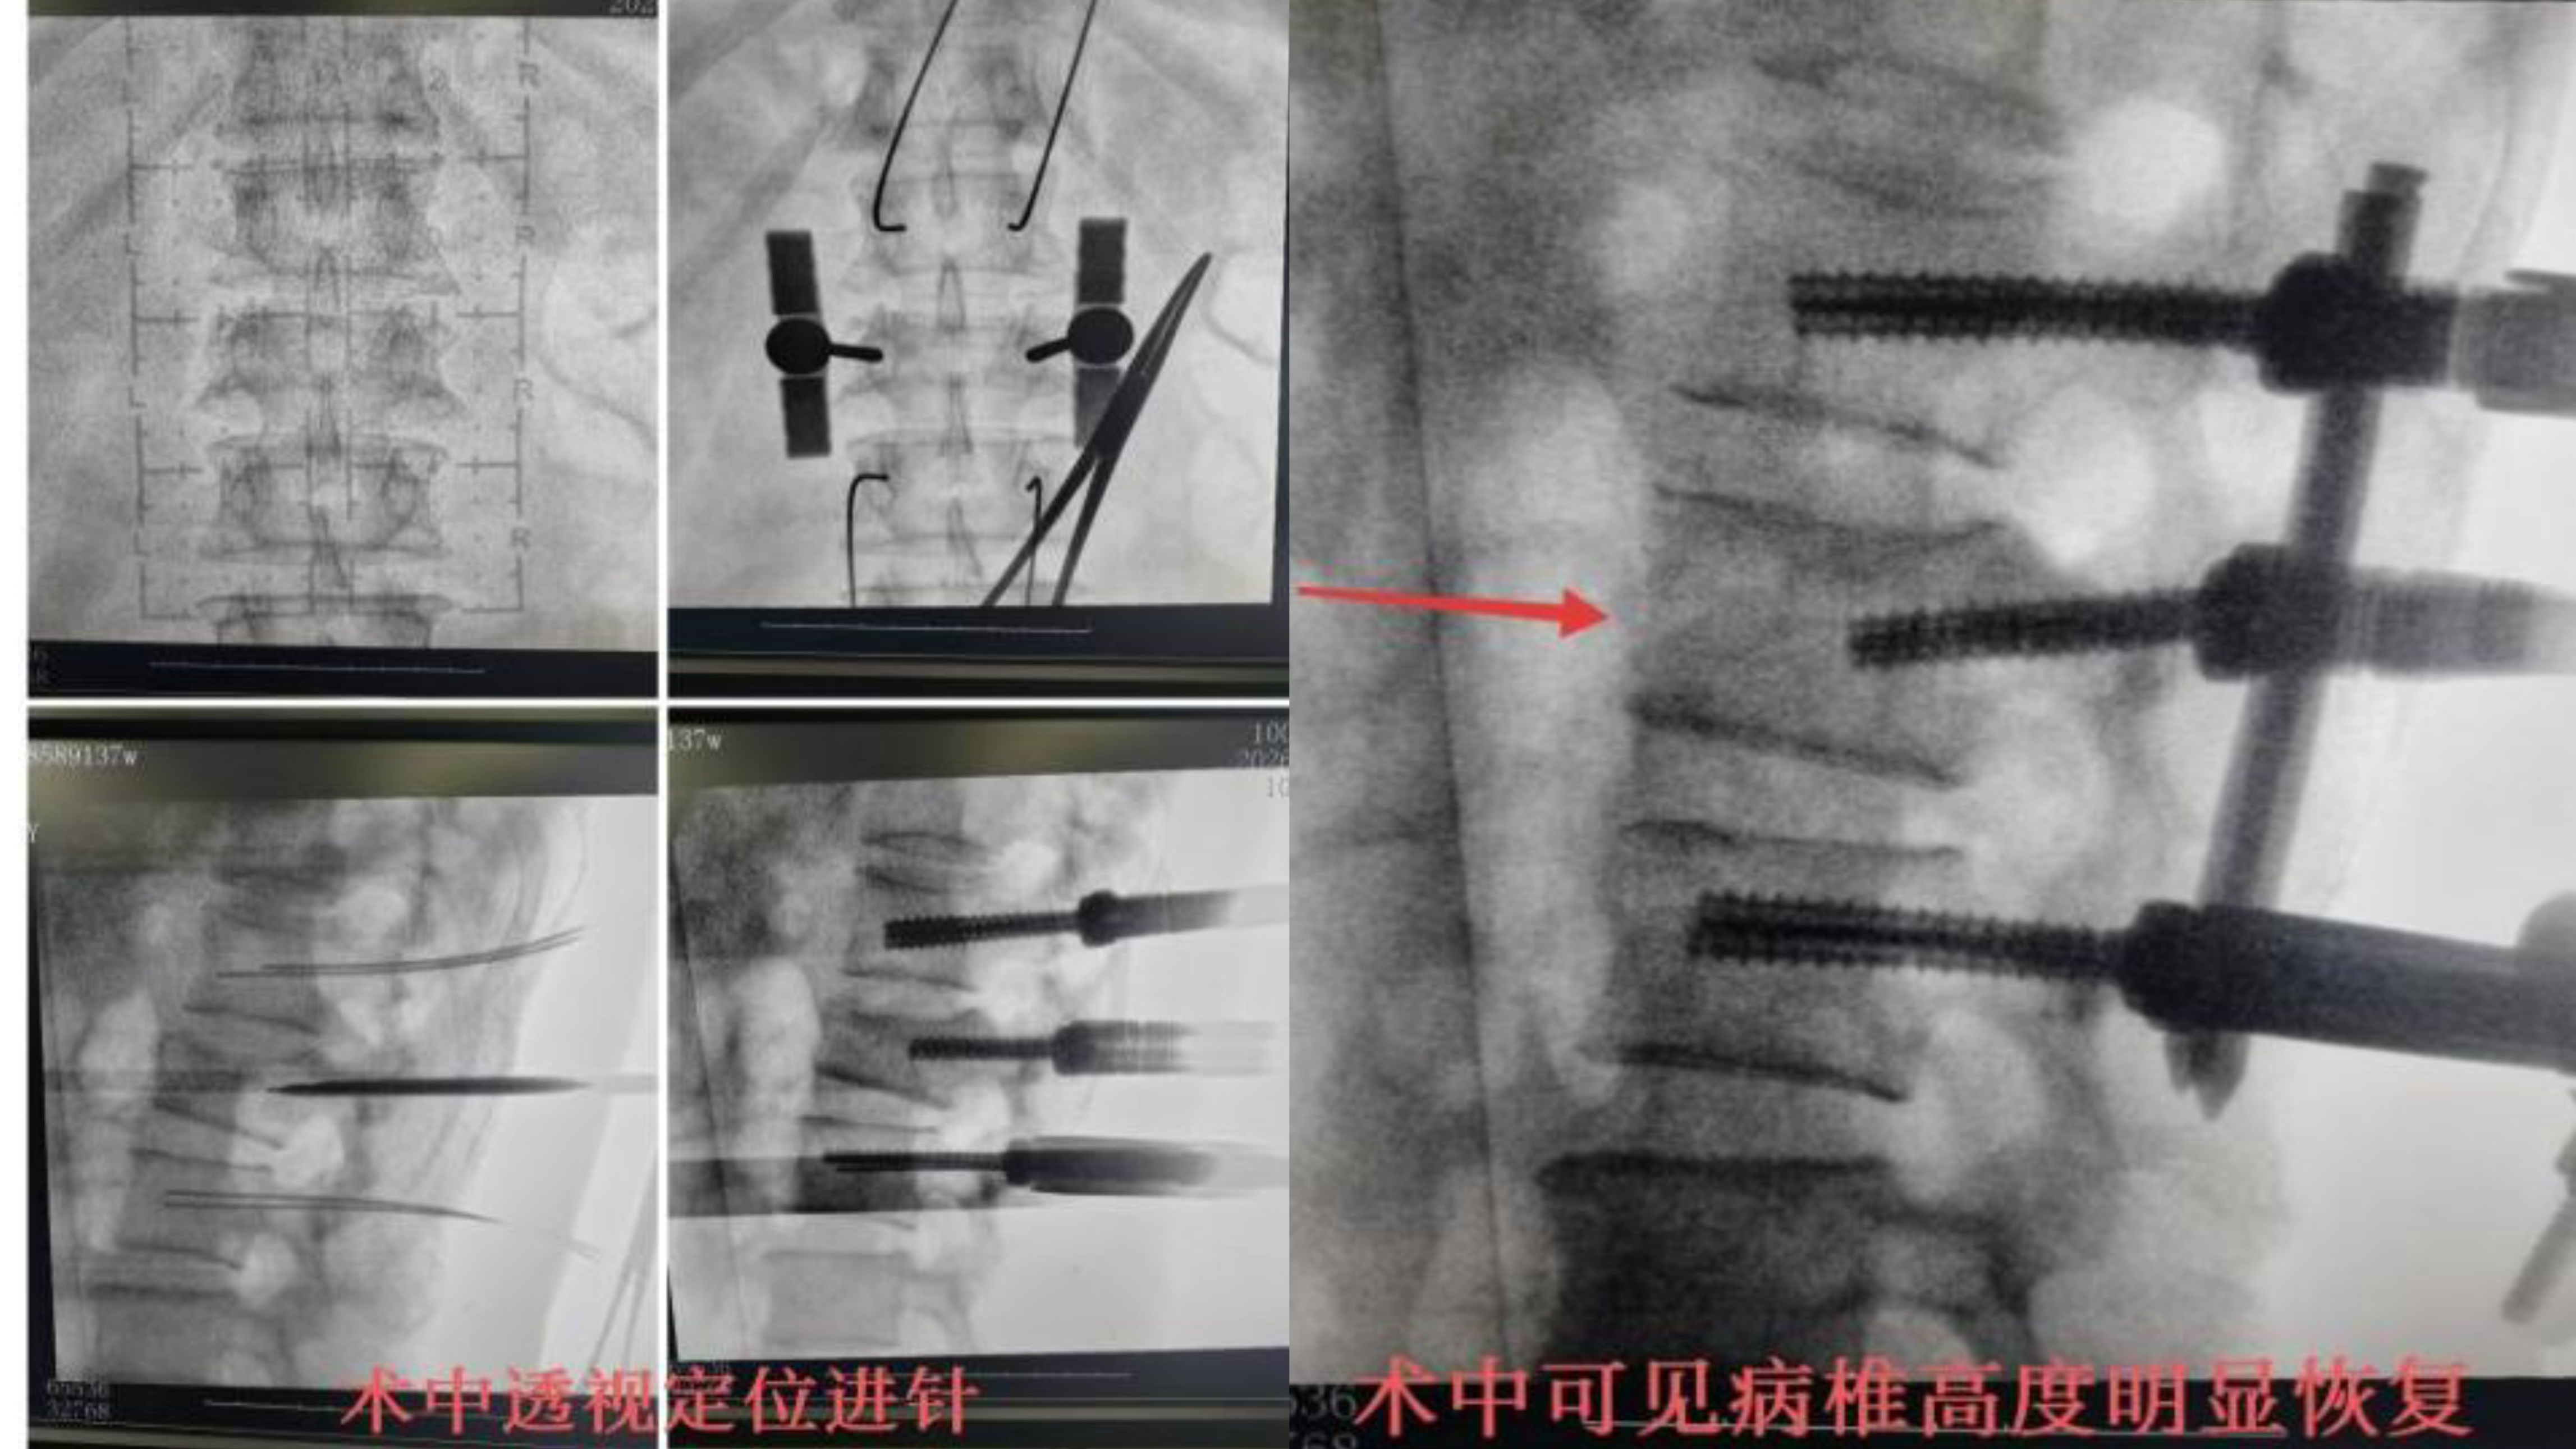

患者李某某,男,59岁,系“摔伤致腰背部疼痛伴活动受限2小时余”入院;入院后予以完善相关检查,CT示:腰2椎体爆裂性骨折,侵占部分椎管,L2左侧横突骨折。MRI提示:L2椎体压缩性骨折,L2右侧椎板骨折;腰椎退行性变;L2/3、L5/S1椎间盘突出。摄片提示:L2椎体楔形改变,椎体前缘压缩1/3。

骨伤一科陈孝贵主任指出:根据患者病史、体征及影像学表现,患者腰椎压缩性骨折(L2 爆裂性)诊断明确,对于脊柱骨折保守治疗患者,需要长期卧床,极易出现褥疮、坠积性肺炎、下肢静脉血栓形成、肺栓赛等并发症,保守治疗椎高丢失会引起腰椎后凸畸形、慢性腰疼及继发腰椎不稳等后遗症,对于该患者,手术指针明确,手术目的:恢复椎高及清理椎管占位,促进早期下地,减少并发症及远期后遗症。建议患者行微创手术治疗方案-经皮椎弓根螺钉复位内固定术,患者及其家属同意并积极配合治疗方案,积极术前准备,在排除手术禁忌后,陈主任为其行手术治疗,手术顺利,术后2天即可佩戴支具下床活动。